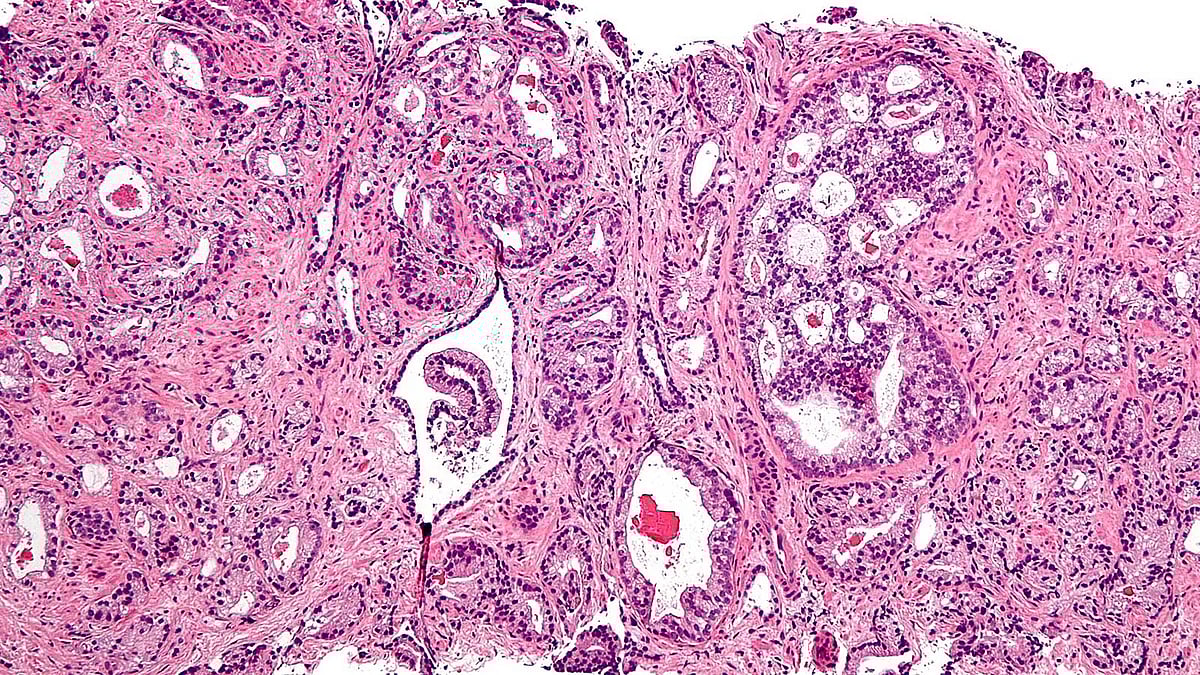

এসব পরীক্ষায় প্রোস্টেট ক্যানসার সন্দেহ হলে মলদ্বার দিয়ে বায়োপসির মাধ্যমে ক্যানসার শতভাগ নিশ্চিত হওয়া যায়।